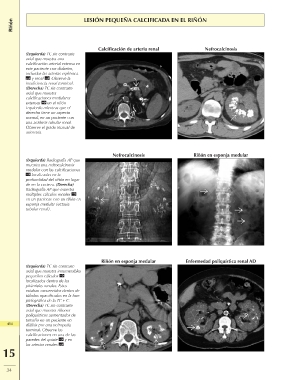

Riñón LESIÓN PEQUEÑA CALCIFICADA EN EL RIÑÓN

(Izquierda) TC sin contraste Calcificación de arteria renal Nefrocalcinosis

axial que muestra una Riñón en esponja medular

calcificación arterial extensa en

este paciente con diabetes,

incluidas las arterias esplénica

y renal . Observe la

insuficiencia renal terminal.

(Derecha) TC sin contraste

axial que muestra

calcificaciones medulares

extensas en el riñón

izquierdo mientras que el

derecho tiene un aspecto

normal, en un paciente con

una acidosis tubular renal.

Observe el grado inusual de

asimetría.

(Izquierda) Radiografía AP que Nefrocalcinosis

muestra una nefrocalcinosis

medular con las calcificaciones

localizadas en la

profundidad del riñón en lugar

de en la corteza. (Derecha)

Radiografía AP que muestra

múltiples cálculos renales

en un paciente con un riñón en

esponja medular (ectasia

tubular renal).

(Izquierda) TC sin contraste Riñón en esponja medular Enfermedad poliquística renal AD

axial que muestra innumerables

414 pequeños cálculos

localizados dentro de las

15 pirámides renales. Estos

estaban oscurecidos dentro de

túbulos opacificados en la fase

pielográfica de la TC + C.

axial que muestra riñones

poliquísticos aumentados de

tamaño en un paciente en

diálisis por una nefropatía

terminal. Observe las

calcificaciones en una de las

paredes del quiste y en

las arterias renales .